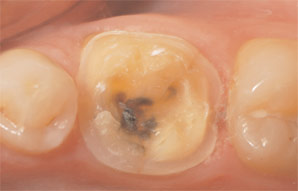

It was decided that the appropriate shade for the patient’s restoration was A3, and a suitable block was selected in size 14 (Empress CAD LT, Ivoclar Vivadent, Amherst, NY). The patient was anesthetized with 1.5 carpule Septocaine 4% with 1:100 epi, after which the failing amalgam and all fracture lines were removed. The preparation was designed to satisfy the conservative requirements of all-ceramic materials, including 1.5 mm to 2 mm occlusal reduction and a shoulder margin of ideally 1.2 mm in width (Case 1, Figure 2). Note that maintaining the margin above the gingival margin facilitates easy clean up and continued hygiene maintenance by the patient.